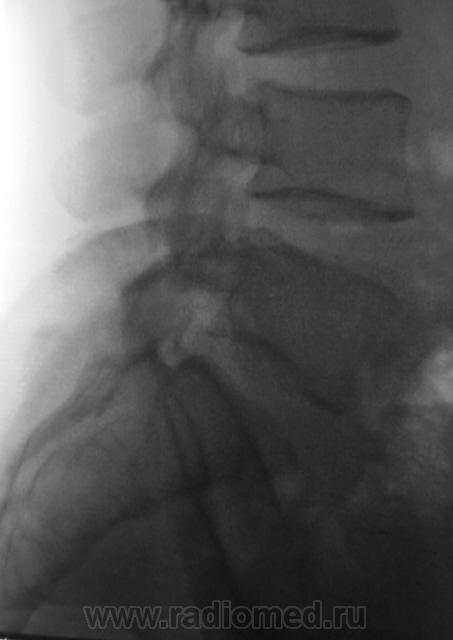

Пациент с болями в пояснице, направлен на рентгенологическое исследование поясничного отдела позвоночника.

задний спондилолистез L3,L4. сакрализация L5.признаки остеохондроза.аномалия тропизма L3-L4 справа ,L5 с обеих сторон.

При всем уважении к коллеге stovbav, лестничный микроретролистез L-2-L-3-L-4 может инициировать такие боли в спмне, что "мама, не горюй". А удлинение задне-нижних углов тел L-3,L -4 запросто могут оказаться косвенными признаками дорсальных протрузий диска..

Теперь на счет расчерчивания. Вот, что я себе нафантазировал. Совершенно две разные картины.Хотя небольшой уступ все таки получился.

"Теперь на счет расчерчивания. Вот, что я себе нафантазировал. Совершенно две разные картины. Хотя небольшой уступ все таки получился."

Ничего, Вы себе не нафантазировали, Игорь Иванович. В данном случае "двуконтурности" заднего края отдельных позвонков не избежать, так как на рентгенограмме в прямой стандартной проекции (снимок выполнен стоя), вроде-бы, как-бы намечается некоторое искривление позвоночника во фронтальной плоскости. Конечно, это никакое не искривление, это просто ротация - 1 - 2 позвонков, и становится понятным, что если 1-2 позвонка чуть ротировались, то на ровность заднего контура всех поясничных позвонков расчитывать не приходится.

О ротации, также свидетельствует различная длина поперечных отростков одноименного позвонка, и это видно.